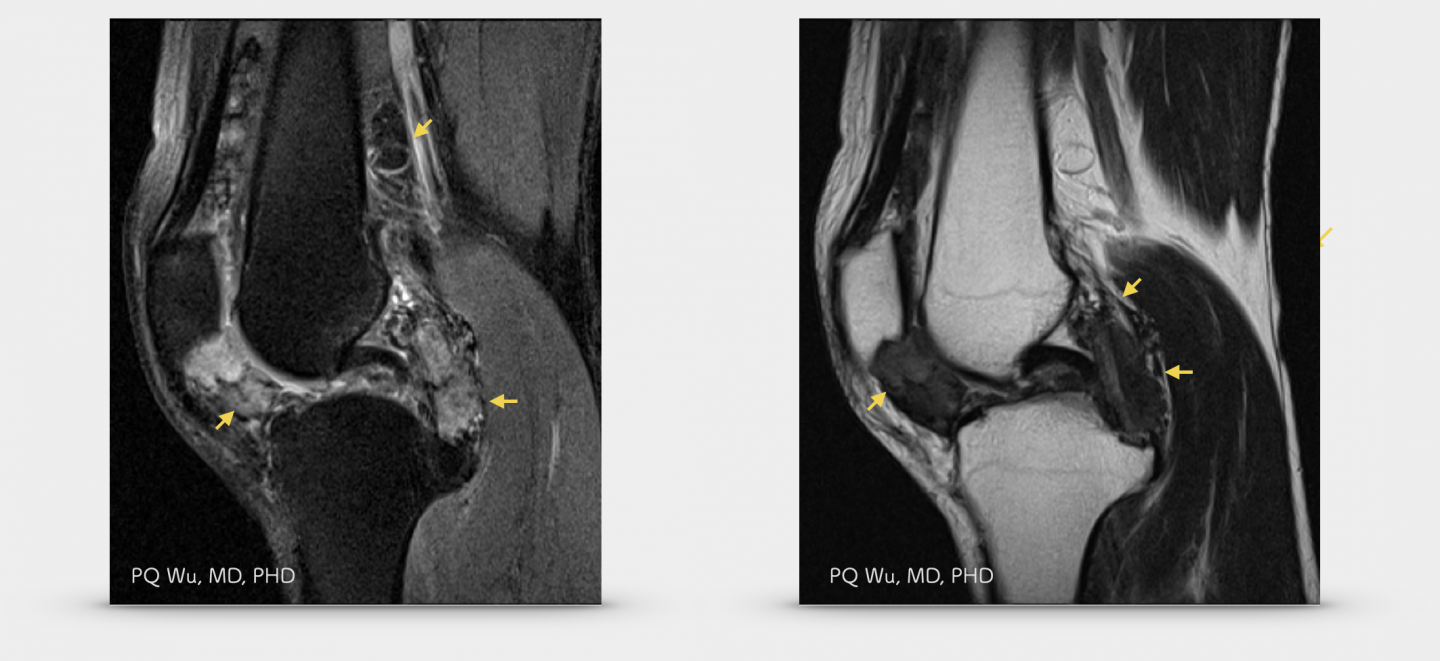

在MRI的影像之中,腱鞘巨細胞瘤最大的特色,便是腫瘤中因為富含大量的血鐵素(hemosiderin),因此在T1與T2訊號中,均會呈現特殊的低訊號,這個特色,使用來區分腱鞘巨細胞瘤與其他的良性或是惡性腫瘤的重要指標。以下為一位46歲男性膝蓋腱鞘巨細胞瘤的影像學表現:

46歲男性,右膝腱鞘巨細胞瘤(MRI)